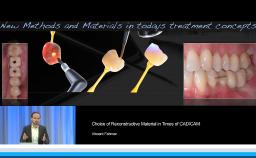

- indicate the different uses of ceramics as final prostheses